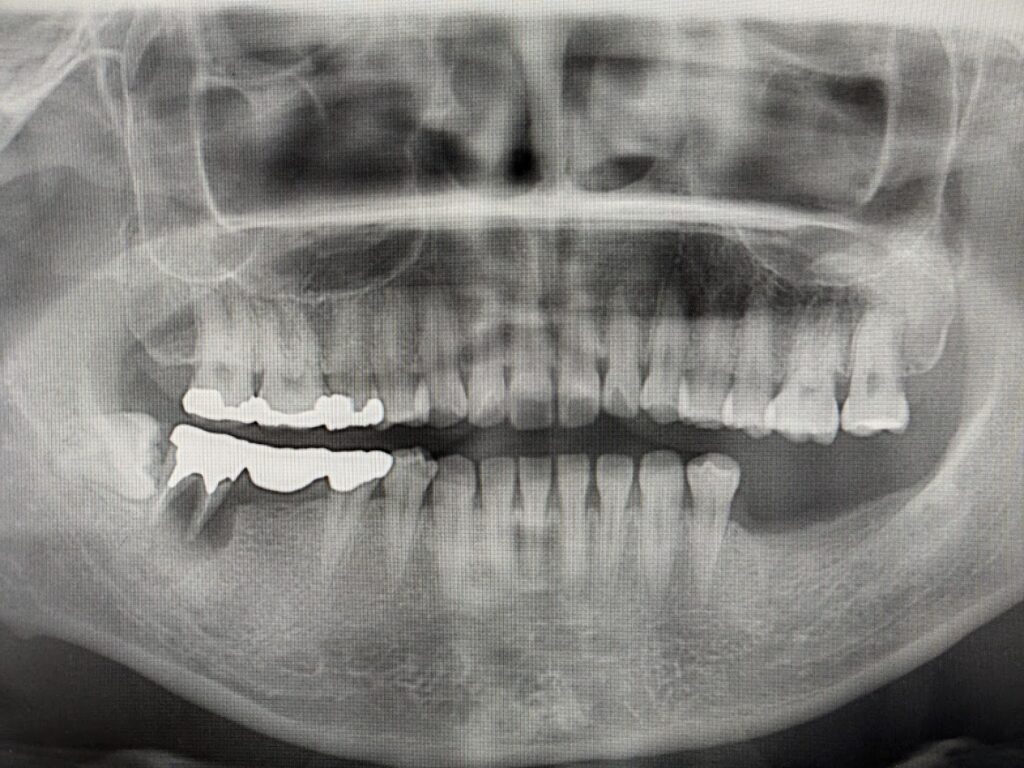

右下のブリッジが痛くて咬めない 歯茎がはれている!との症状で来院されました。ブリッジの支台である第2大臼歯周囲の骨が吸収(画像上真っ黒になっている)しています。

移植後2ヶ月半のデンタルレントゲン写真です。移植した歯は約2周間で根管治療を開始して根管内に水酸化カルシウムを充填しました。